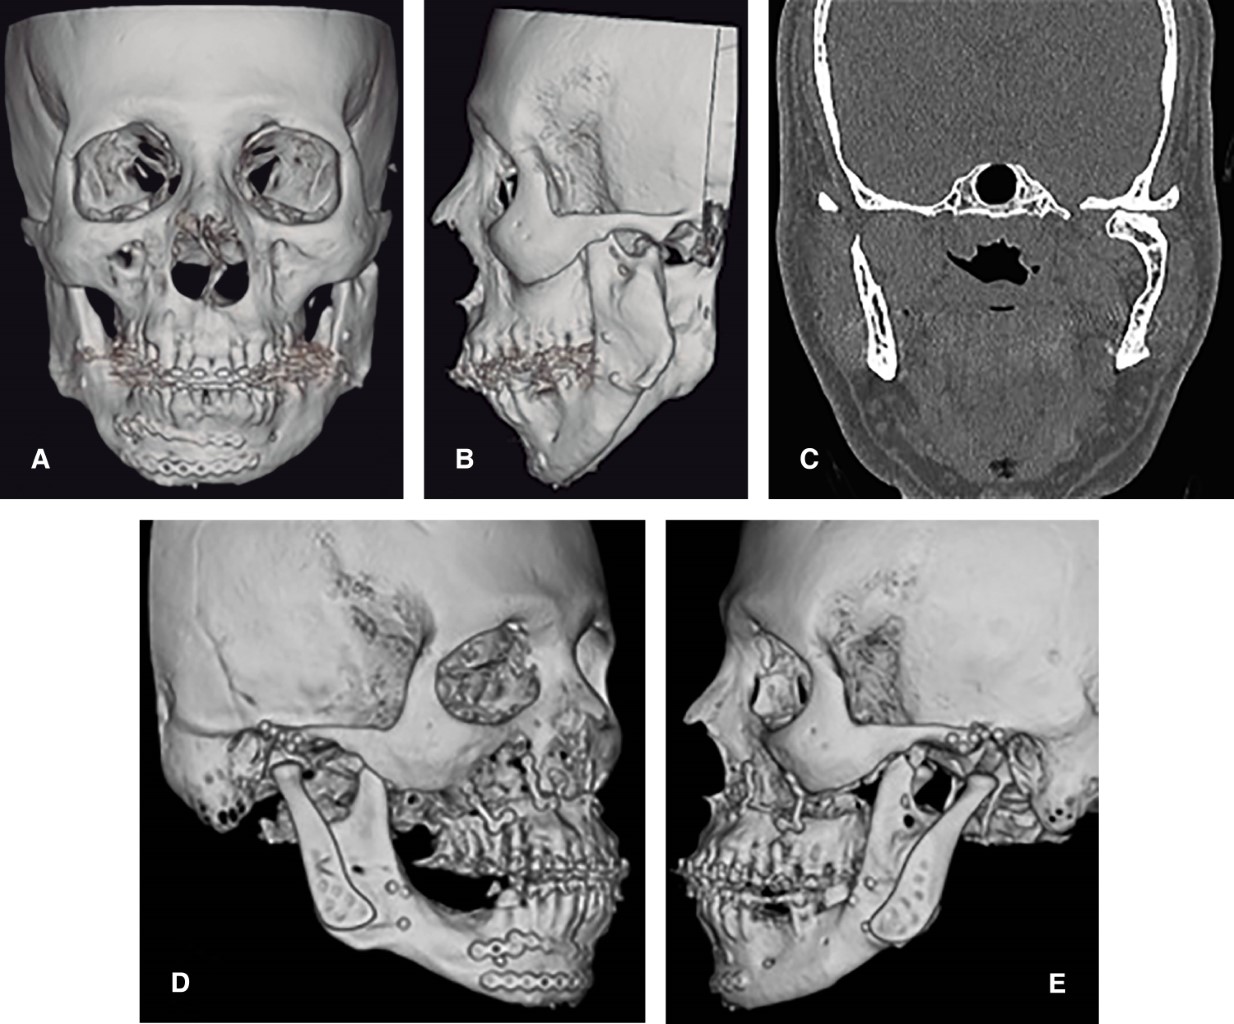

Paciente masculino de 53 años quien presentó fractura de parasínfisis mandibular derecha y condilar bilateral en año 2001. Se realizó reducción abierta y fijación interna (RAFI) parasinfisiaria derecha y FIM con arcos de Erich durante cuatro semanas como parte del tratamiento para la fractura condilar. De forma posterior, presentó retrognatismo mandibular y maloclusión, por lo que requirió osteotomía sagital de rama mandibular bilateral (OSRMB) de avance (2005). Diez años después, presentaba dolor articular severo bilateral, hipometría oral (28 milímetros) con desviación mandibular izquierda y retrognatismo mandibular. La tomografía mostraba el cóndilo mandibular izquierdo fuera de fosa glenoidea, neoformación condilar aberrante y aplanamiento condilar bilateral correspondiendo a estadio Wilkes V (Figura 1), por lo cual se realizó reemplazo de ATM bilateral concomitante con CO bimaxilar consistente en descenso posterior de 10 mm con cuña interposicional en el gap (Figuras 2, 3 y 4). Durante cinco años de seguimiento continúa con oclusión estable, sin dolor, apertura oral de 40 mm.

Figura 1

Figura 2

Figura 3

Figura 4